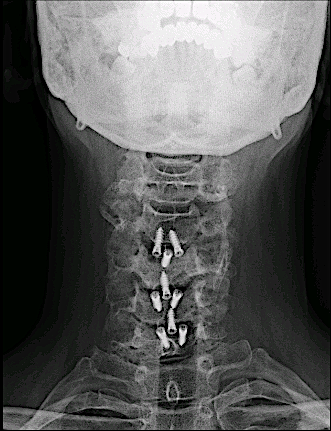

A los dos años consultó nuevamente por presentar clínica de dolor cervical irradiado a MMSS. Tras descartar recidiva, se decidió intervenir la estenosis de canal vía anterior.

Rx 6 meses